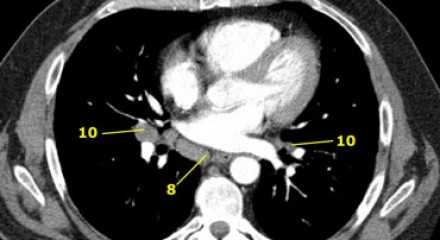

8. Параэзофагеальные лимфатические узлы

Эти лимфатические узлы ниже подкаринальных лимфатических узлов и распространяются каудальнее до диафрагмы. На изображении слева ниже уровня карины справа от пищевода обозначен лимфатический узел 8 группы.